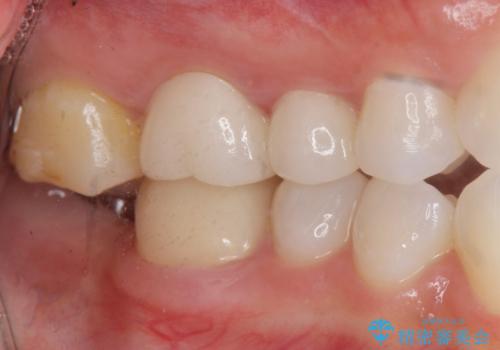

奥歯のインプラント治療

- 右下の奥歯を虫歯で喪失しそれ以来よく物が噛めず、改善を求めて来院されました。

入れ歯かインプラント治療のご提案を行い、よりしっかりとかめるインプラント治療を希望されました。

骨との結合する期間が早く、大きな咬合力にもしっかりと耐えることのできるストローマンインプラントを用いた咬合機能回復を計画します。

- 44万円(ストローマンインプラント・チタンカスタムアバットメント・仮歯・フルジルコニアクラウン)費用は治療当時の料金となります